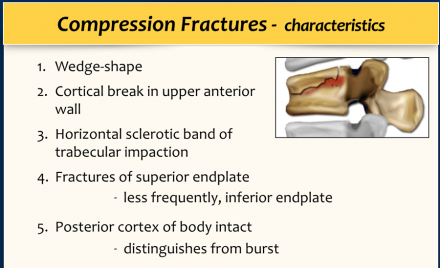

A simple compression fracture is the most common form of injury and is seen in 90% of cases.

It is either loss of height of the anterior part of the vertebral body or disruption of the vertebral endplate.

The posterior cortex of the vertebral body has to be intact and this feature differentiates a simple compression fracture from the more severe burst fracture.

The posterior cortex may bulge slightly posteriorly in a simple compression fracture. As long as there is no free fragment with posterior displacement, it is a wedge compression fracture and not a burst fracture.

The images show a compression fracture.

All we see is a cortical disruption in the upper anterior wall of the vertebral body and slight loss of height ventrally.

The posterior vertebral cortex is intact.

The sagittal reformatted image also shows the cortical disruption.

Notice that on a 2.5mm axial slice you can miss these fractures.

You have to look at the thin slices to detect such a subtle fracture.

Notice the horizontal band of density, which is often described as sclerosis.

This density does not mean that it involves an older fracture that is already healing with sclerosis.

This is merely a sign of trabecular impaction in an acute fracture.